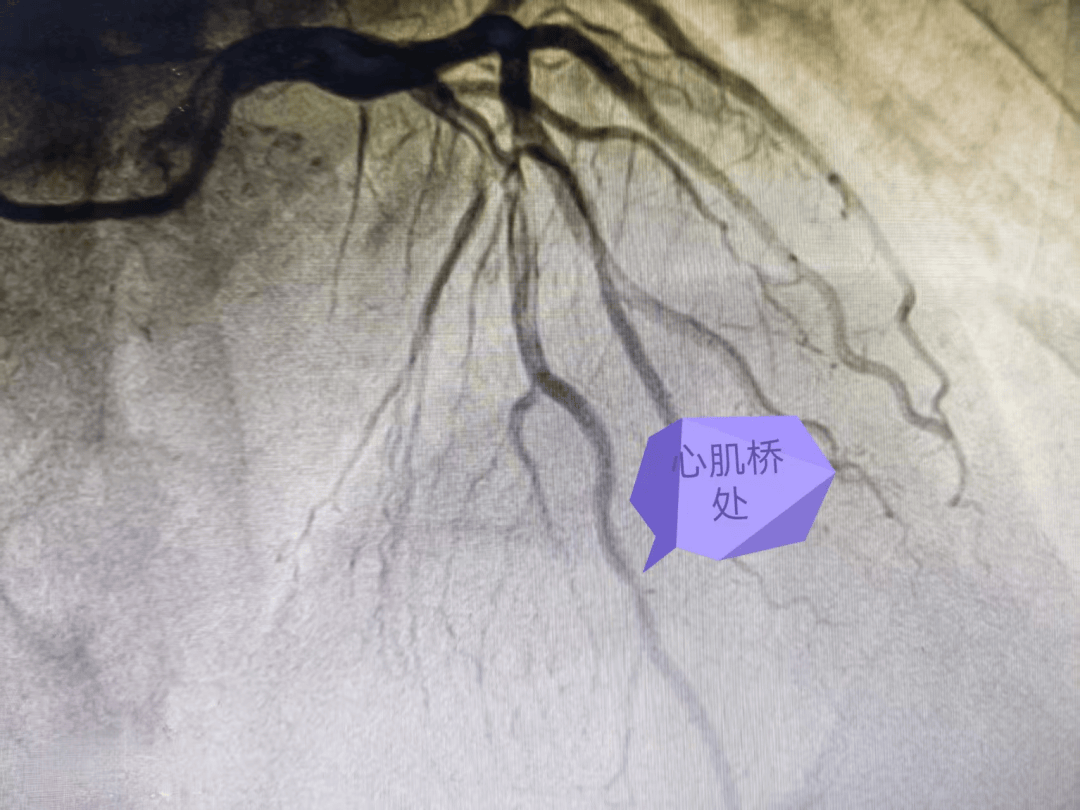

前降支心肌桥疑致急性心肌梗死一例

心肌桥

心肌桥,或称心肌桥冠状动脉,是一种较为常见的先天性冠状动脉畸形